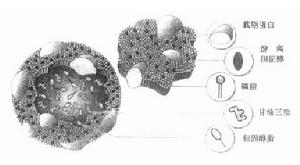

性激素的生物合成複方炔諾孕酮片-330:每片含炔諾酮0.3mg、甲基炔諾酮0.3mg、炔雌醇0.03mg。口服避孕片0號:每片含炔諾酮0.3mg、甲地孕酮0.5mg和炔雌醇0.035mg。口服避孕片0號:每一小格含藥同上。